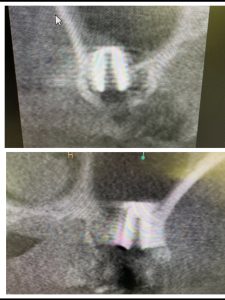

朝より、ソケットリフト

患者さんの希望により左右同時に!

非常に侵襲が少ない術式だからオッケー👌

異物は一切入れないデンサーリフト!

難なく40分で終わり、値も良く6w後には仮歯

印象予定